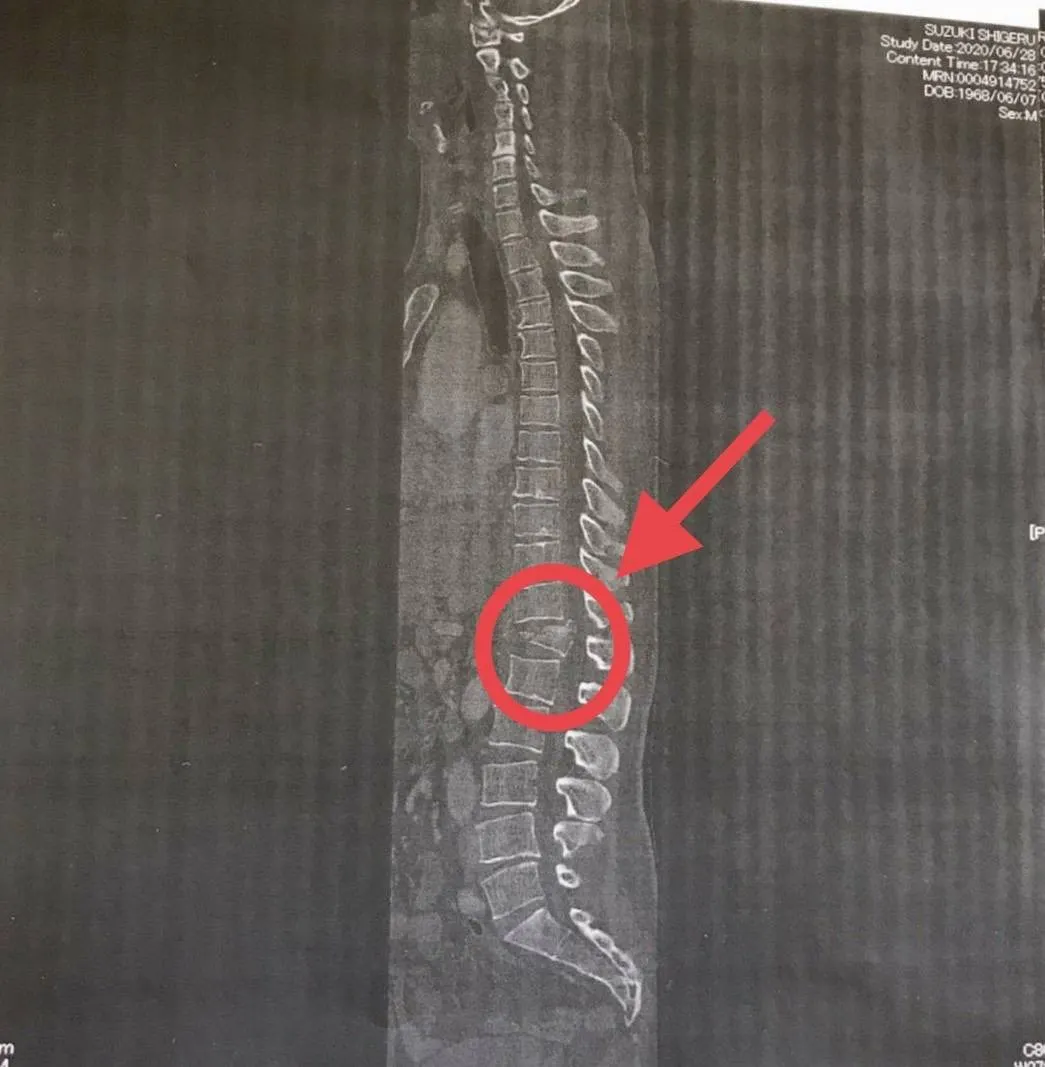

手術は無事終わり地獄のようなリハビリが開始され私生活にも支障が出るほどつらい毎日だった。実際のレントゲン写真が残っている。着地の衝撃で背骨が砕け押し出されているのがわかる。押し出された背骨が脊髄をさらに押し出し神経までも損傷した。